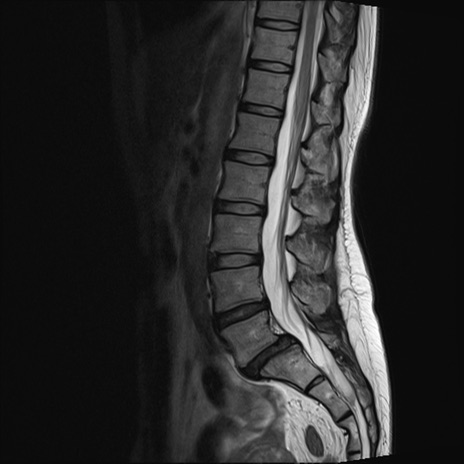

【整形】TIPS症例4 腰椎MRI T2WI(矢状断像)

腰椎MRI

T1WI(矢状断像)